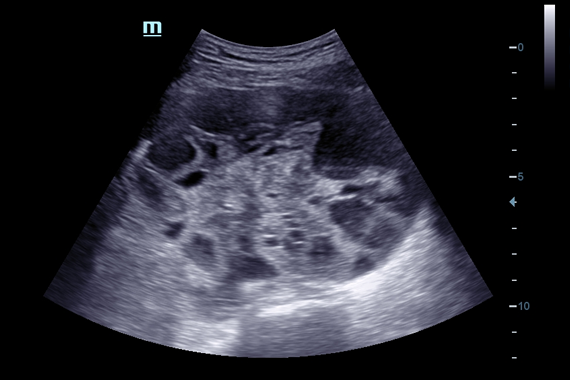

• Abdominal package - предустановленные параметры, аннотации, маркеры, программы измерений для абдоминальных исследований

• Конвексный датчик Mindray C6-2

• Конвексный датчик Mindray 3C5A

• Микроконвексный датчик Mindray 6C2